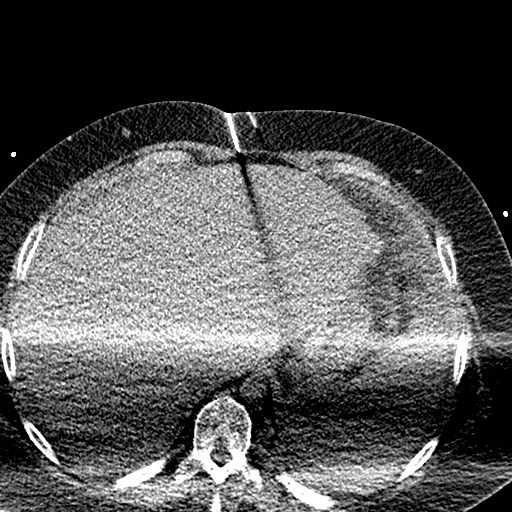

Case 3

20 F with PMH hypoplastic left heart s/p fenestrated Fontan procedure admitted for shortness of breath and hypoxia of uncear etiology.

145/58 mmHg / 78 bpm / 20 breaths/min / 97.6°F / 88% 6L

Faint expiratory wheezing in upper lungs, rhinorrhea, and congestion

AST 33, ALT 33, Alk Phos 222